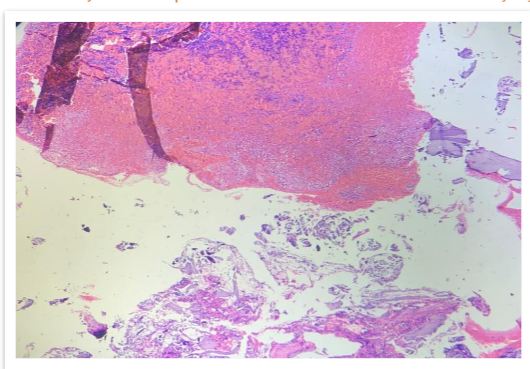

The MRI findings showed multiple focal altered signal intensity lesions (Figure 2). A bone biopsy was performed, and histopathological examination revealed the presence of plasma cells.

Immunohistochemistry showed plasmacytoid cells are positive for CD 138 (Figure 6). The patient was diagnosed with non-secretory multiple myeloma.